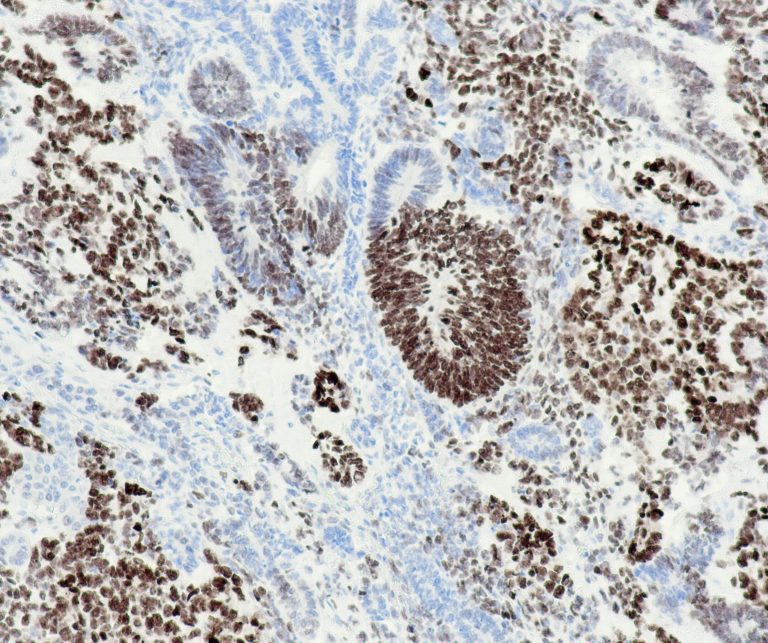

Gastrointestinal (GI) Pathology

General Marker